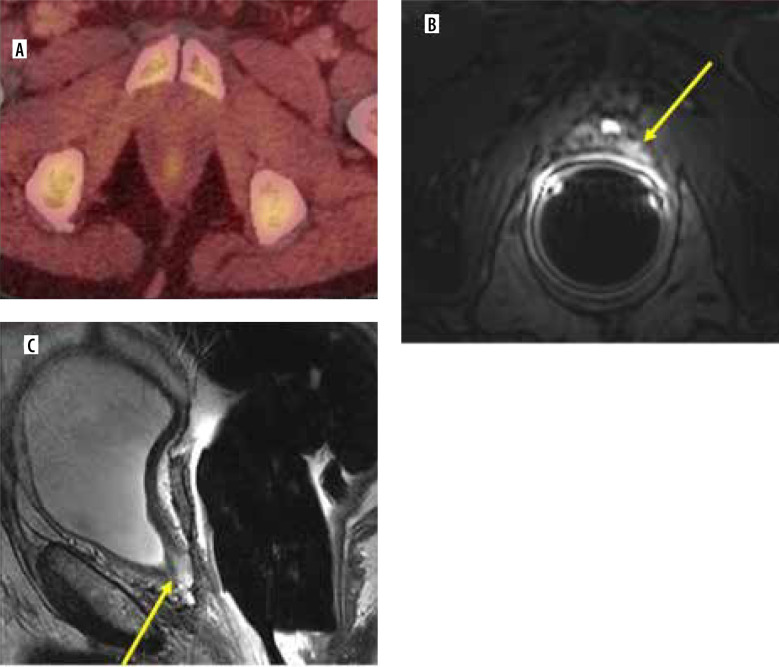

Abstract Image